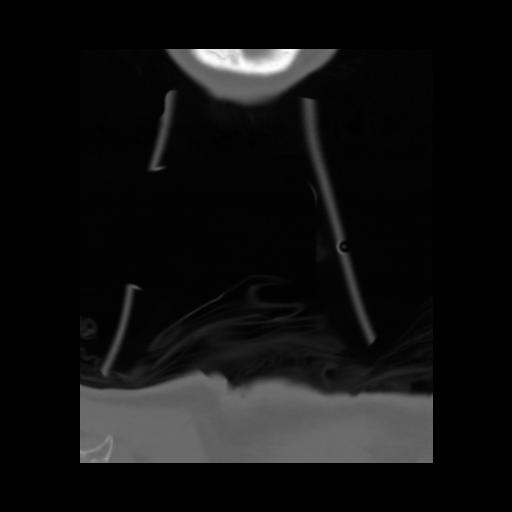

13 P.BLANDAS,,Coronal,2.000,P.BLANDAS,Coronal,